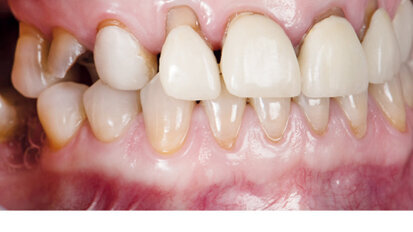

Nový úsměv za jeden den

Čt. 28. května 2020